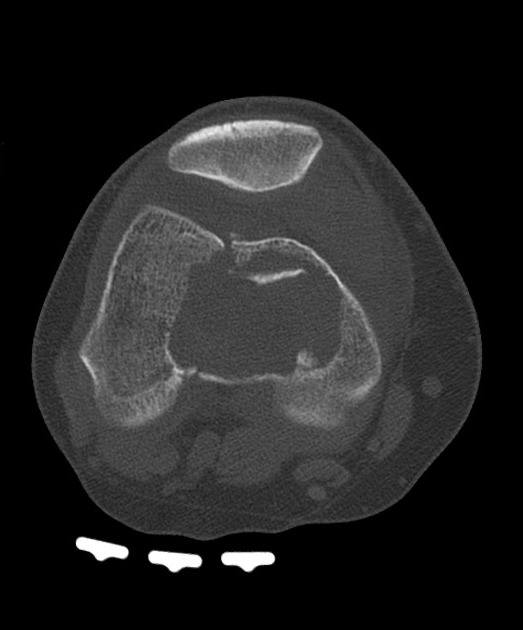

U tế bào khổng lồ

» Thông tin: Nữ giới – 31 tuổi.

» Lâm sàng: Đau khớp gối.